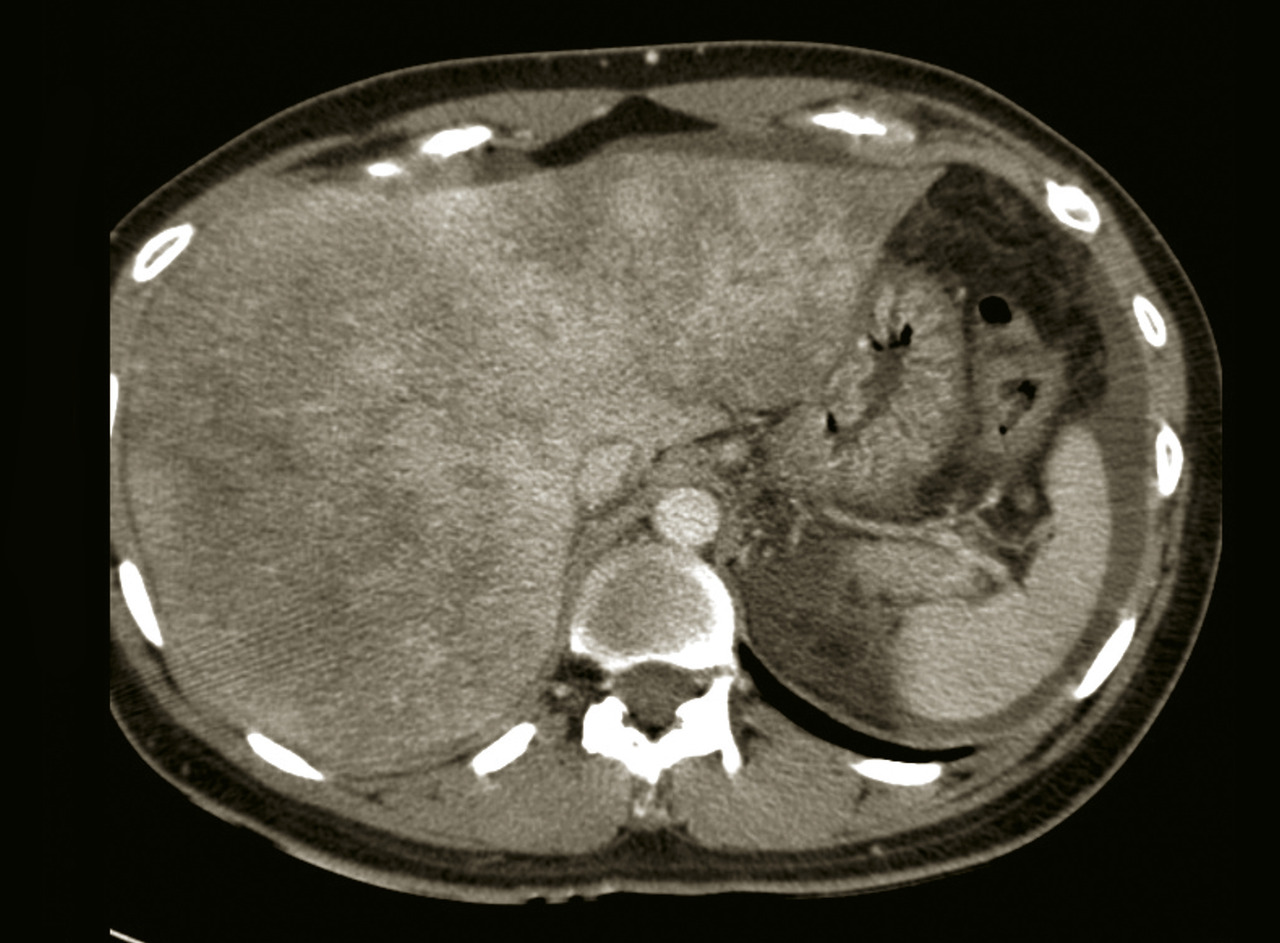

L’échographie abdominale est l’examen d’imagerie de première intention devant la découverte d’une hépatomégalie. Elle permet de caractériser cette dernière plus finement que l’examen clinique, de mettre en évidence des signes de cirrhose (dysmorphie hépatique à contours bosselés, signes d’hypertension portale : splénomégalie et voies de dérivation porto-systémiques), une dilatation des voies biliaires, une stéatose hépatique (parenchyme hyperéchogène), et le mode Doppler peut montrer des signes indirects d’insuffisance cardiaque droite (dilatation des veines hépatiques) ou encore une thrombose d’une ou plusieurs veines hépatiques responsable d’un syndrome de Budd-Chiari. L’échographie permet aussi de mettre en évidence une ascite, même si elle est de faible abondance, ainsi qu’un ou plusieurs nodules hépatiques.

Une imagerie en coupe, tomodensitométrie (TDM) ou imagerie par résonance magnétique (IRM), avec étude triphasique (temps artériel, portal et tardif) après injection de produit de contraste, peut être utile au diagnostic étiologique d’une hépatomégalie.